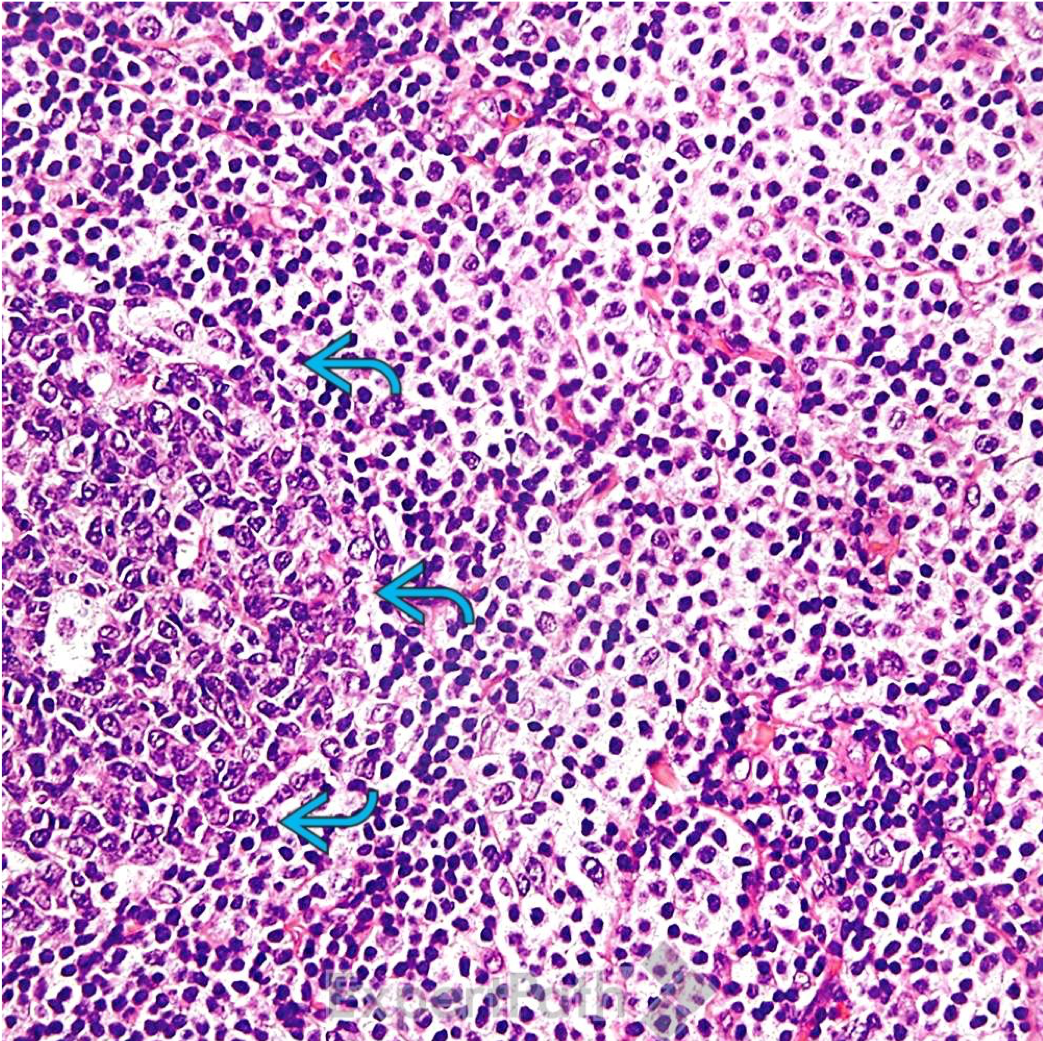

Diagnosis?

toxoplasmosis